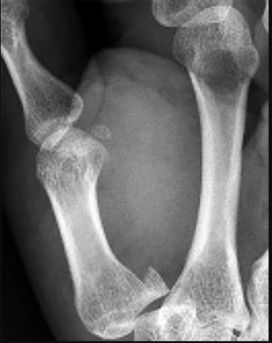

ORTHOPEDIC MCQS 011 UPPER EXTREMITY 2011 Upper Extremity Self-Assessment Exam by Dr.Dhahirortho 1 Question 1…